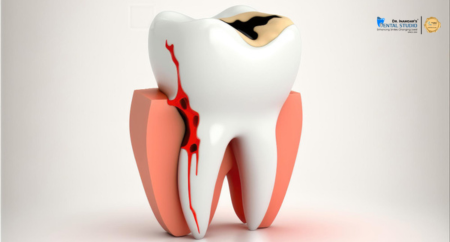

General dentistry is dedicated to maintaining your oral health with routine check-ups, professional cleaning, and effective fillings. Our preventive care services are designed to ensure a healthy and radiant smile, addressing issues before they become problems and keeping your teeth and gums in optimal condition.